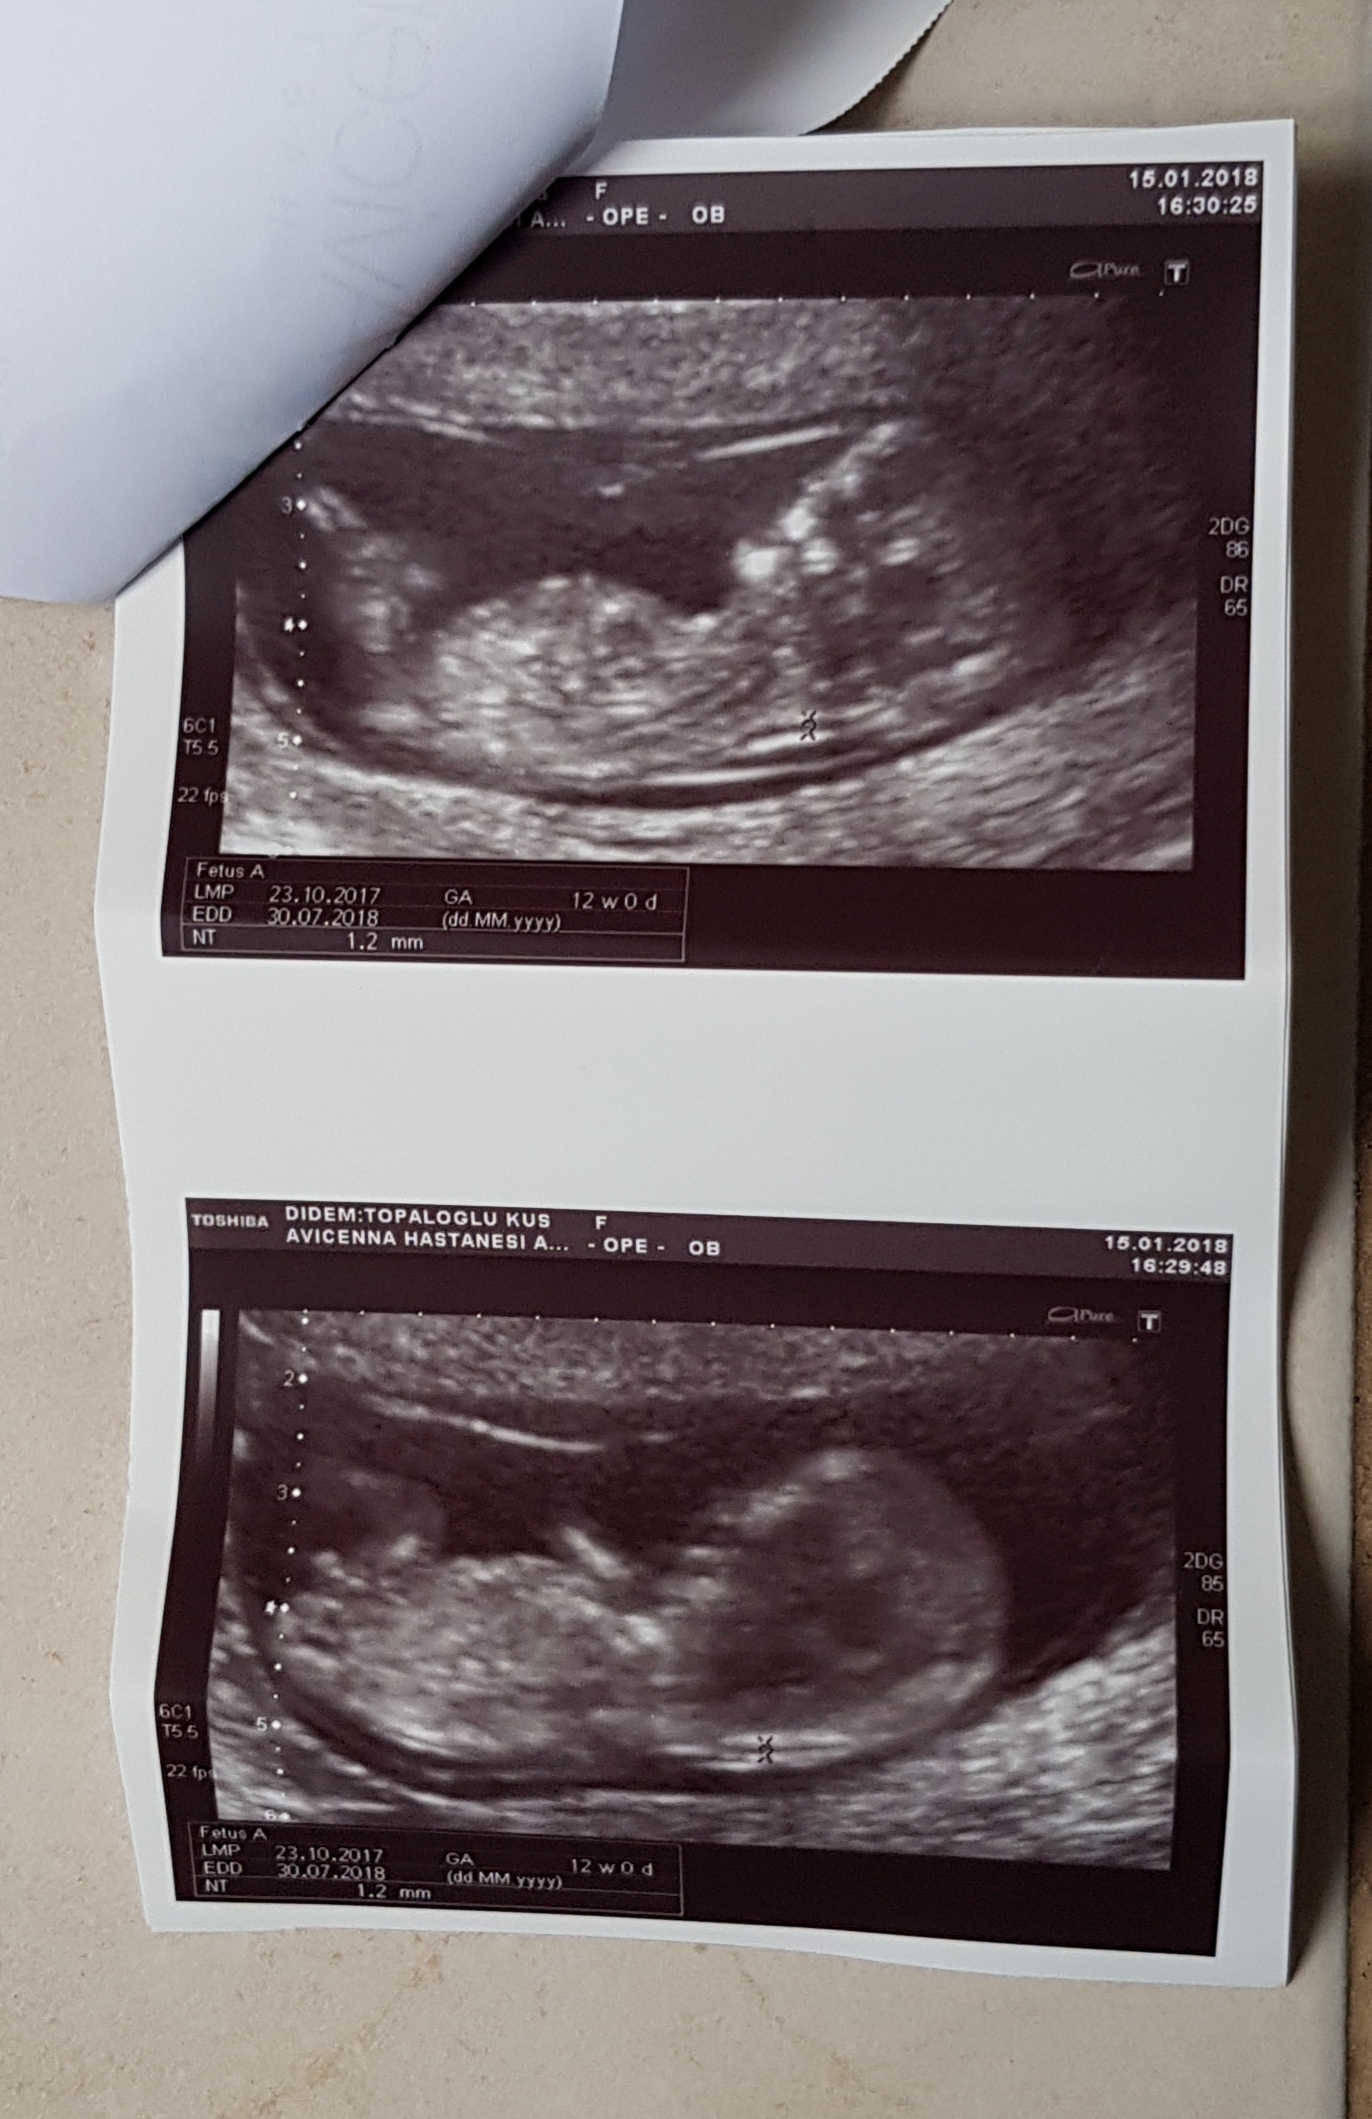

• 20180116_131632.jpg

20180116_131632.jpg

2,7 MB · Görüntüleme: 944

Anlaşılan o ki bebek süpriz yapmak istiyor. Evet burda da belli değil. Hayırlısı olsun. 16-17 -20 . haftalar da net olarak bebeğinizin cinsiyetini öğrenebilirsiniz. 12-13 . haftalarda cinsiyet tahminin de yanılmalar olabiliyor. Sağlıklı gebelik geçirmeniz dileği ile.

13 haftalikken erkek dedi doktor 13+6 kiz gibi dedi benimde kafam karisti🙂 bir hafta sonra tekrar gidicem 16+4 olacak o zaman netlesir insaAllah.tekrar tesekkur ederim ♡

Doktorlar ultrasonla anlık olarak cinsiyeti görebilir. Size verilen görseller de anlardan bir kesit. Doktorun gördüğü anla size verilen usg görüntüsü farklı olabilir. Belirttiğim gibi 12-13 haftalarda cinsiyet tahminleri yanıltıcı olabilir. Bir kaç koşul yanılmaya neden olabilir. Bir daha ki kontrolde bebeğin pozisyonu uygunsa cinsiyetini öğrenebilirsiniz. Rica ederim, sevgiler.

Merhaba, emin olmamakla birlikte bebeğinizin cinsiyetinin erkek olduğu kanaatindeyim. Bebeğinizin cinsiyetini net olarak 16-17-20. haftalarda öğrenebilirsiniz.